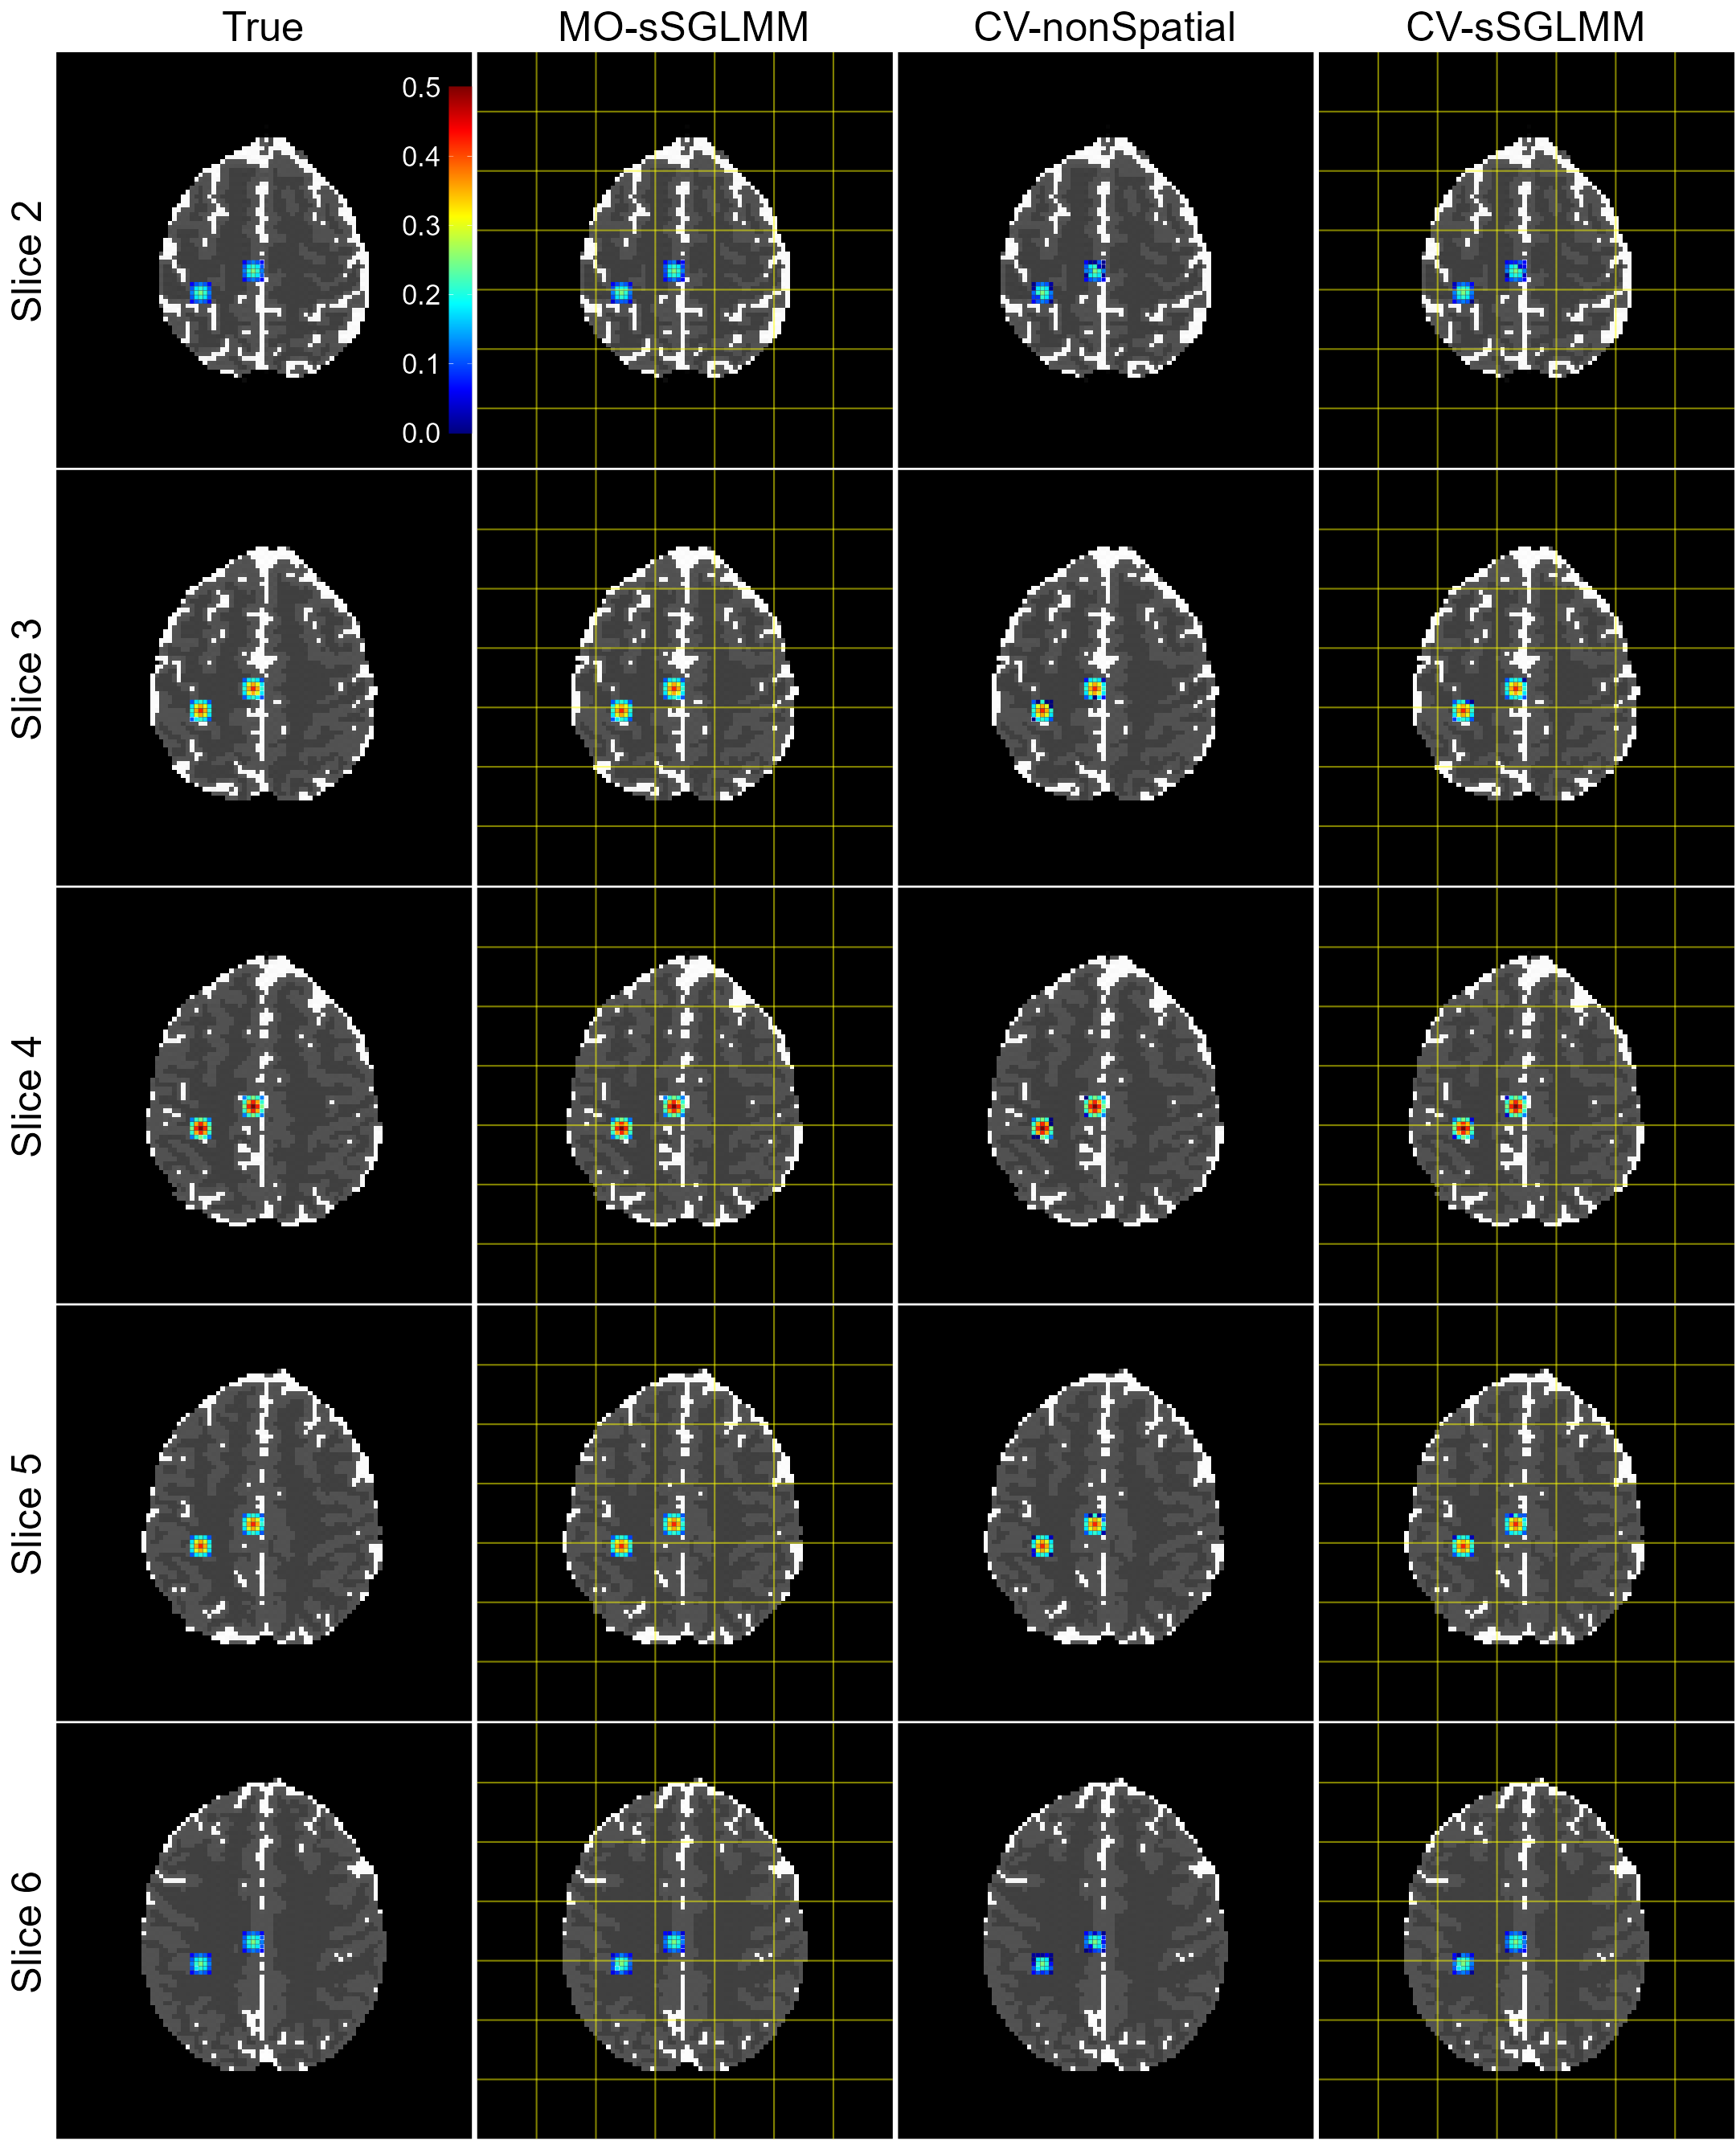

Activation then decreases from slice 4 to slices 3 and 5 and is weakest in slices 2 and 6. Slices 1 and 7 exhibit no activation. It’s important to note that, with dynamic phase, the model from Lee et al. (2007) is not equivalent to that from Rowe (2005b) as indicated in Rowe (2009). This discrepancy suggests the proposed model is under model misspecification in this scenario. However, as both βRevsuperscriptsubscript𝛽𝑅𝑒𝑣\beta_{Re}^{v} and βImvsuperscriptsubscript𝛽𝐼𝑚𝑣\beta_{Im}^{v} in model (2) include magnitude and phase information, and given that prior studies (Yu et al., 2018, 2023) have used the Lee et al. (2007)-based model to process this dataset, we deem it worthwhile to test our model on these data. We set G=49𝐺49G=49 and a threshold of 0.8722 for both MO-sSGLMM and CV-sSGLMM, with ψ𝜓\psi set to Φ1(0.50)superscriptΦ10.50\Phi^{-1}(0.50) and Φ1(0.11)superscriptΦ10.11\Phi^{-1}(0.11), respectively. For CV-nonSpatial, the threshold is set to 0.5, again following the advice of Yu et al. (2018). Activation maps are presented in Figure 6. We indeed observe that our model tends to overestimate the magnitude. Since the magnitudes are overestimated, we scale the estimated magnitude to the range of true magnitude in the corresponding slice. True and (scaled) estimated magnitude maps are displayed in Figure 7.

Further numerical results, displayed in Table 4, show a pattern of the CV-sSGLMM model outperforming both the MO-sSGLMM and CV-nonSpatial models across different slices in terms of detecting true positives (TP). It should be noted, however, that the MO-sSGLMM model achieves a 100% precision (no false positives, FP) for most slices, albeit at the cost of a low recall rate (high false negatives, FN), indicating that the model is more conservative in identifying activated voxels. For the CV-nonSpatial model, although it exhibits good precision across the slices, the recall rates remain lower, specifically in the slices with weaker activation strengths (slices 2 and 6). This performance pattern suggests that the model struggles to detect activations in areas with low CNR, highlighting a limitation when dealing with real-world fMRI datasets that often feature low CNR. In comparison, the CV-sSGLMM model consistently detects a higher number of true positives across all slices, demonstrating a stronger detection power even in slices with weak activations (slices 2 and 6). This underscores the benefit of incorporating spatial information, which enhances the model’s capacity to detect weaker activations in the presence of complex noise conditions. The model also maintains a 100% precision across all slices, suggesting that the inclusion of spatial information does not lead to an increase in false positives. As anticipated, both the MO-sSGLMM and CV-sSGLMM models, which employ brain parcellation, demonstrate superior computational efficiency, even when the parallel computation is gated by a 16-core CPU. This advantage becomes even more pronounced when handling larger datasets.

Refer to caption

Figure 7: True and (scaled) estimated magnitude maps for a realistic simulation as produced by the MO-sSGLMM, CV-nonSpatial, and CV-sSGLMM models